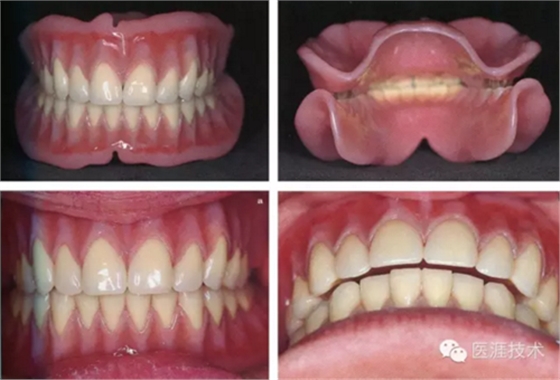

20,制作完成的義齒在頜架上的狀態(tài)

正中頜

前伸頜

21,頜架上調(diào)頜

22,制作完成的義齒,下頜義齒的前庭溝封閉區(qū)的邊緣狀態(tài)

23,制作完成義齒口腔內(nèi)狀態(tài)